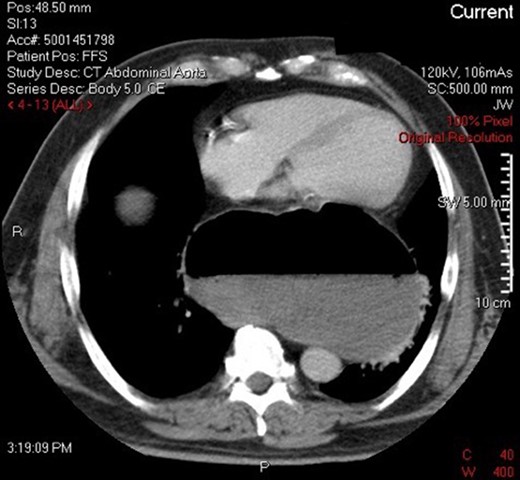

A 69-year-old man with a background medical history significant for hypertension and mild obesity, presented to his local district hospital in remote New South Wales, Australia with sudden onset of severe epigastric pain radiating to his back. He was diaphoretic and pale, and initial assessment of the patient seemed to be that of a man suffering an acute myocardial infarction. Despite this, his initial observations were all within normal limits, and his electrocardiograph revealed a sinus bradycardia and no ischaemic changes. All initial blood examinations, including serum troponin, lactate, liver function tests, renal markers, electrolytes and C-reactive protein were completely normal, with the full blood count revealing only a mild leucocytosis (12.3 × 109/L). Interestingly, the most significant finding came from his initial chest X-ray which showed a large intrathoracic gastric bubble consistent with a large hiatus hernia (Fig. 1). The patient went on to have an intravenous contrast-enhanced computed tomography (CT) scan of the chest and abdomen which revealed an obstructed intra-thoracic stomach incarcerated within a para-oesophageal hernia (Fig. 2). Surgical services in the patient’s local town are limited and thus the patient was transported to the closest regional centre with on-call general surgical services. Decompression with a nasogastric tube (NGT) was attempted but failed.

CT demonstrating obstructed intra-thoracic stomach in mesenteroaxial alignment.